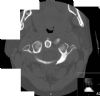

Fracture through the left anterior and posterior arches of the atlas with some lateral displacement of the left lateral mass. Axial CT 2.

Dusch Atkinson - 31/10/2009